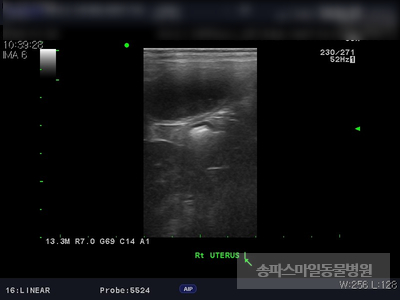

초음파 검사상 자궁의 크기가 매우 확장되었으며 자궁 내부의 액체가 고여있는 것으로 확인되었습니다.

강아지 자궁축농증이 진단되었습니다.